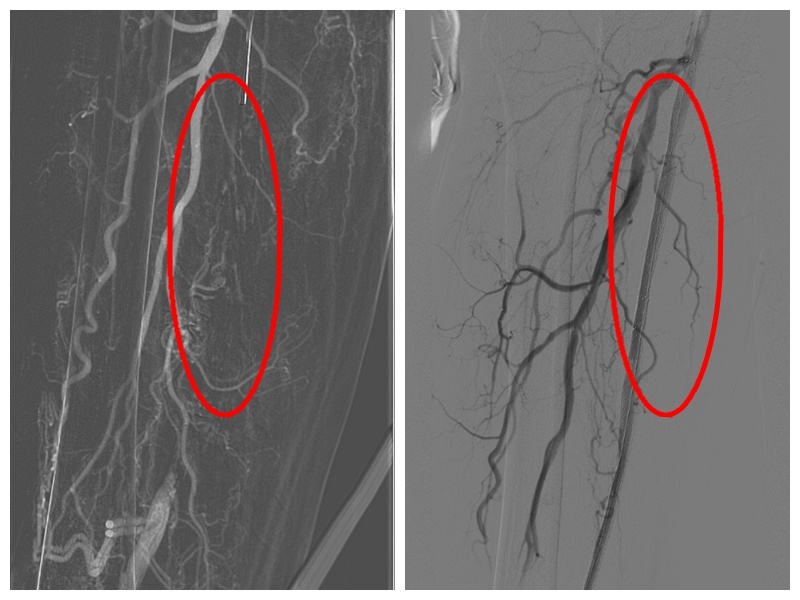

左图术前造影,右图支架置入后

经患者及家属同意,林晖副主任医师联合温医大附一院血管外科黄景勇主任为赵大爷进行了下肢动脉造影,行右侧髂总动脉球扩张术,在血管被撑开后,置入支架,并以球囊扩张的方式成功打通右股浅动脉闭塞,术中共植入3枚支架,血流顺畅。